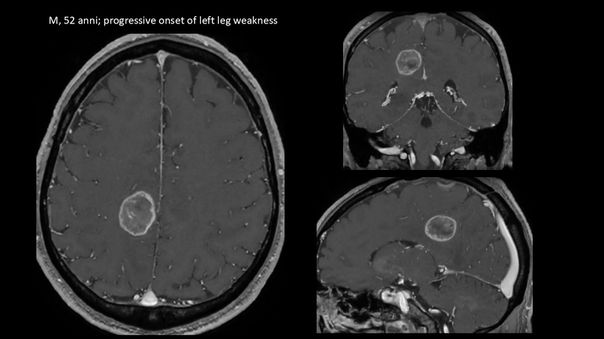

La diagnosi viene eseguita con la Risonanza Magnetica con Mezzo di Contrasto. Nei casi in cui sono coinvolte delle particolari aree funzionali del cervello, viene eseguita anche la RM Funzionale e la Trattografia prima dell’intervento chirurgico.

Glioblastoma parietale destro